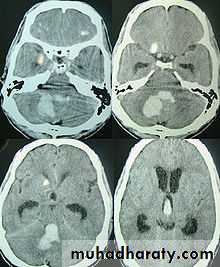

the principle imaging for ICH is CT scanning

Cerebeller 8%

15%Pontine 8%

Pontine or other brainstem intracerebral hemorrhage has a mortality rate of 75% at 24 hours.

Cerebellum - Ataxia